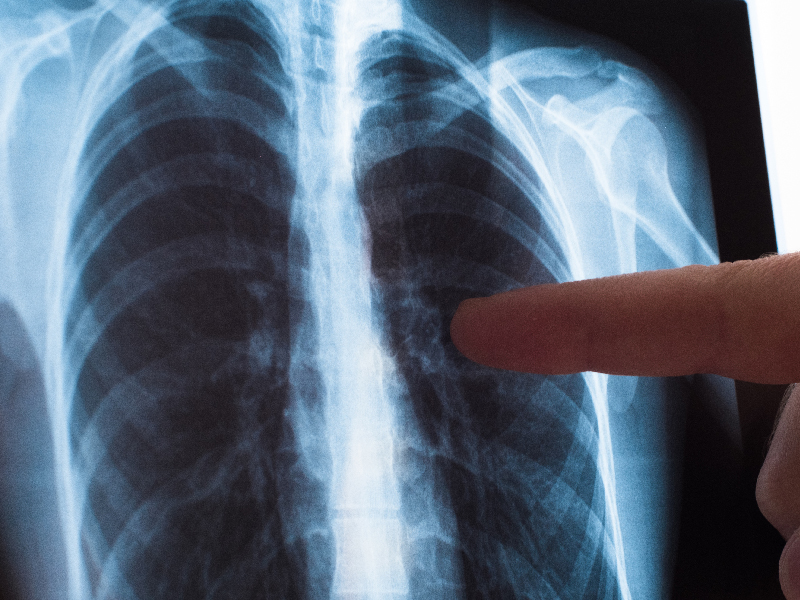

印尼宣布结核病紧急状态

美都新闻网  9 月 30 日电 :人类发展与文化统筹部长普拉提克诺(Pratikno)宣布,我国进入结核病紧急状态,呼吁采取与该国抗击新冠疫情时同等严肃的措施。

根据世界卫生组织发布的《2024年全球结核病报告》,印尼在结核病病例数上位居全球第二,仅次于印度,报告病例109万例,死亡人数12.5万例。